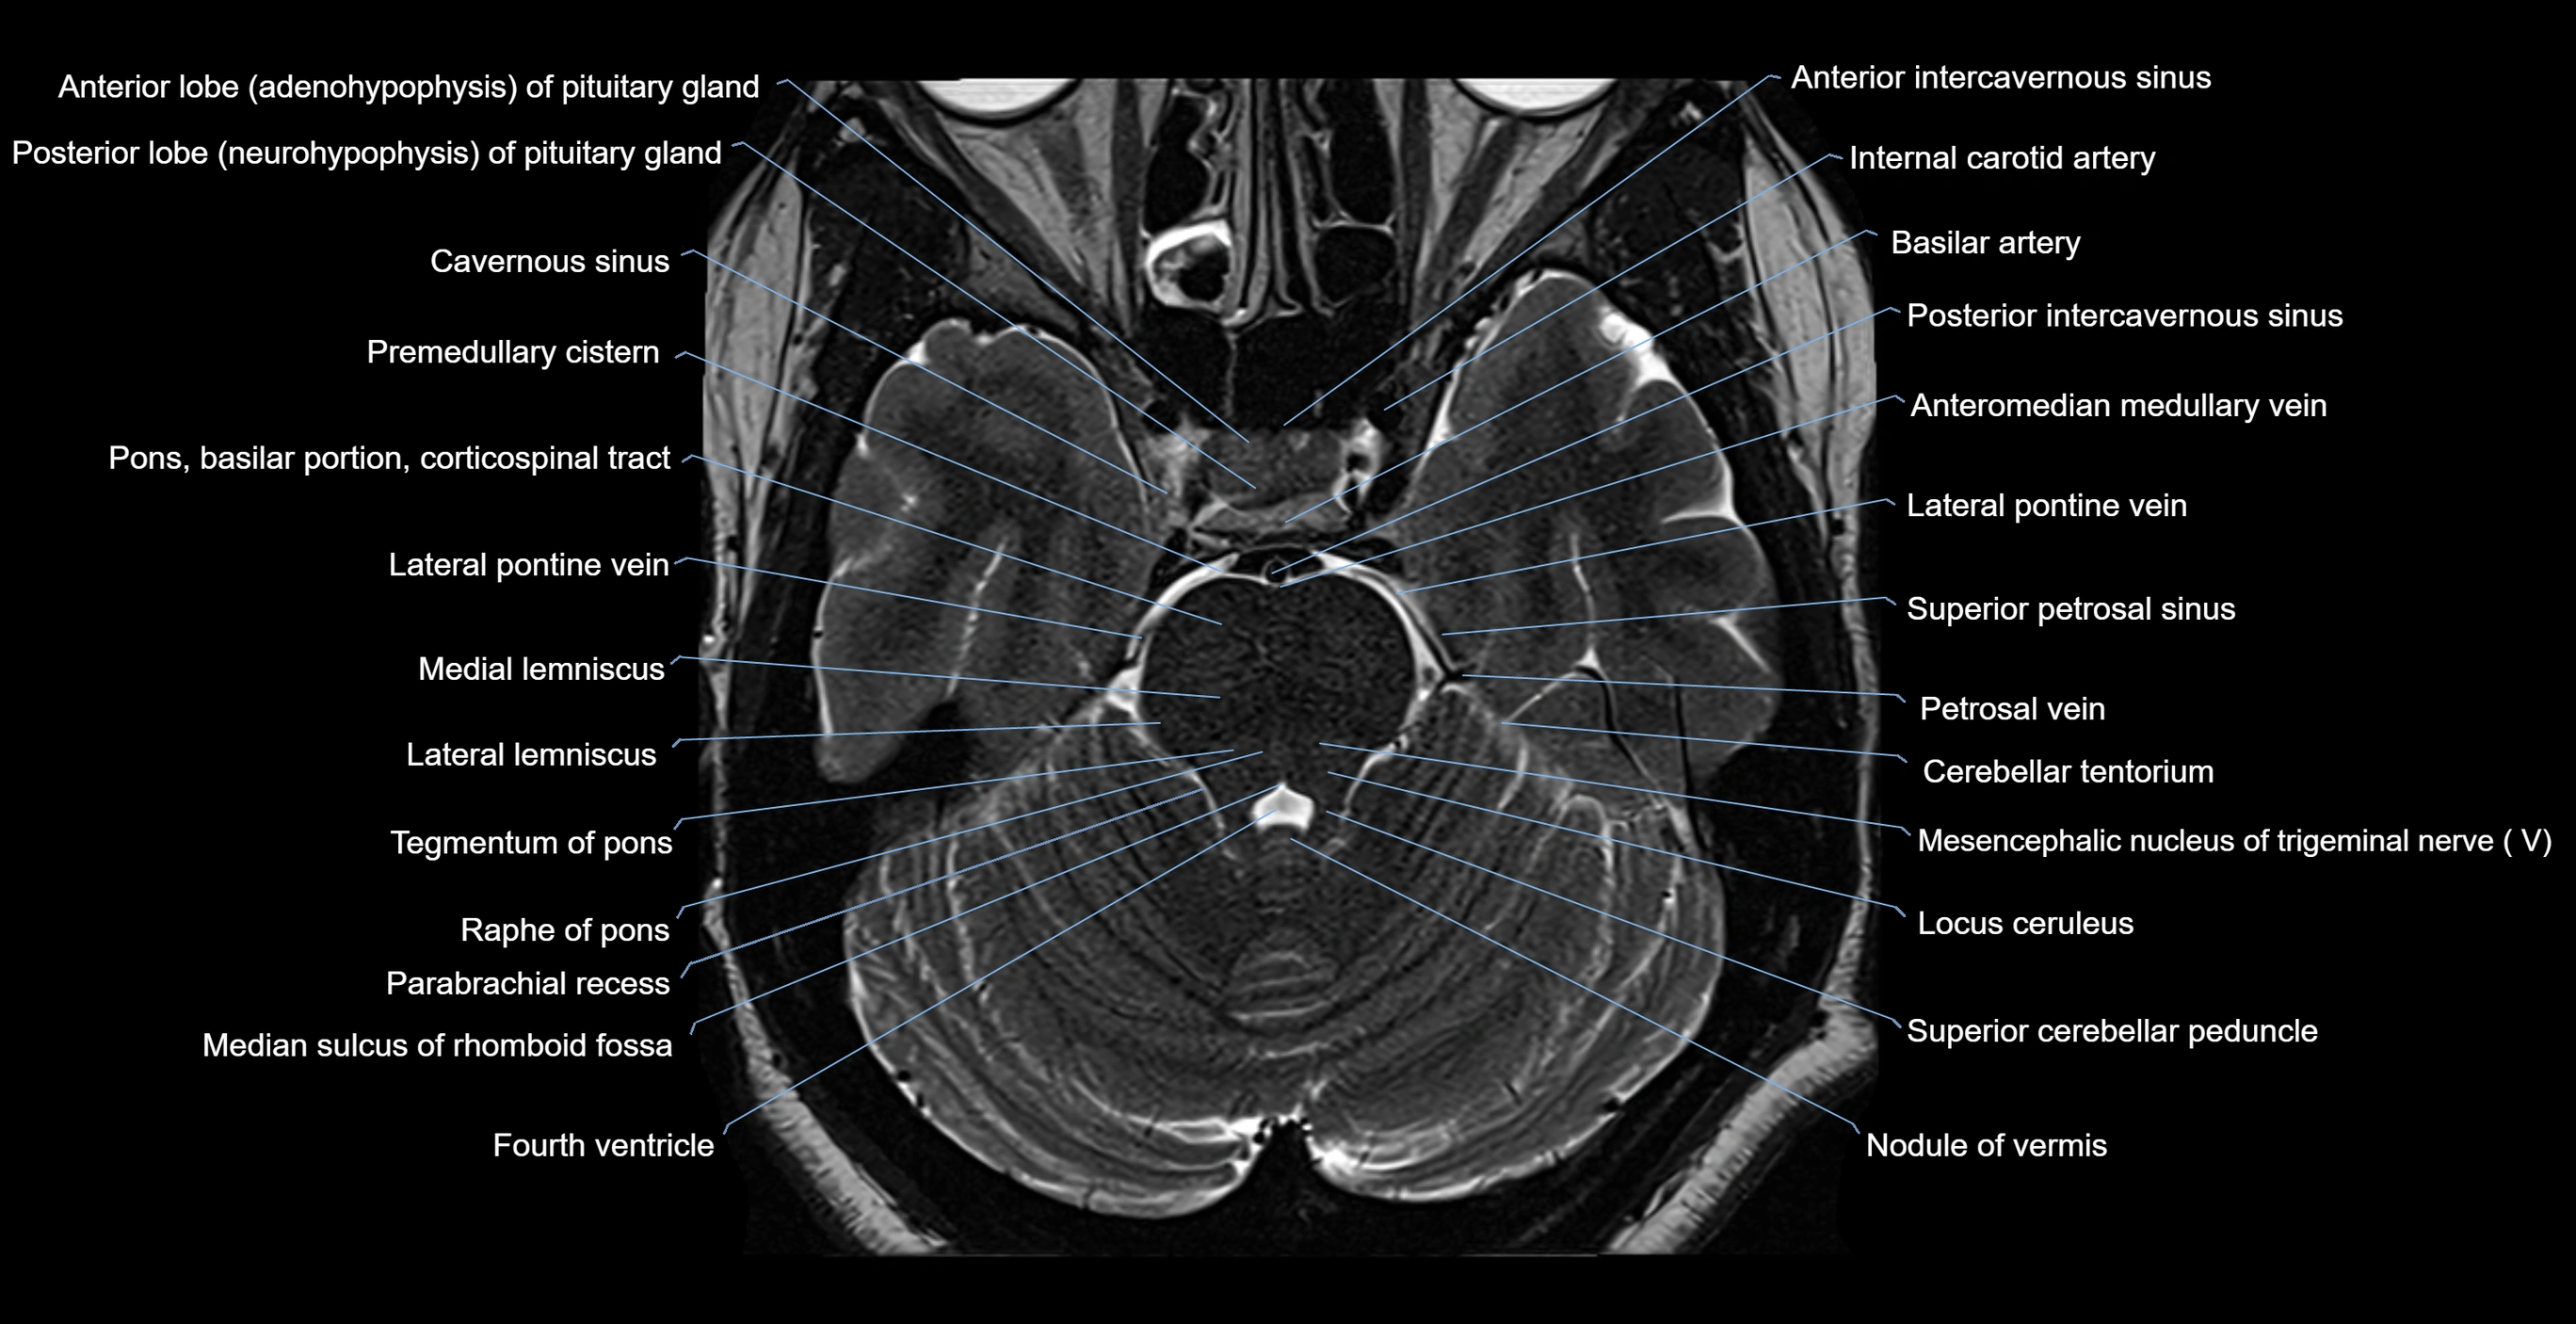

MRI images